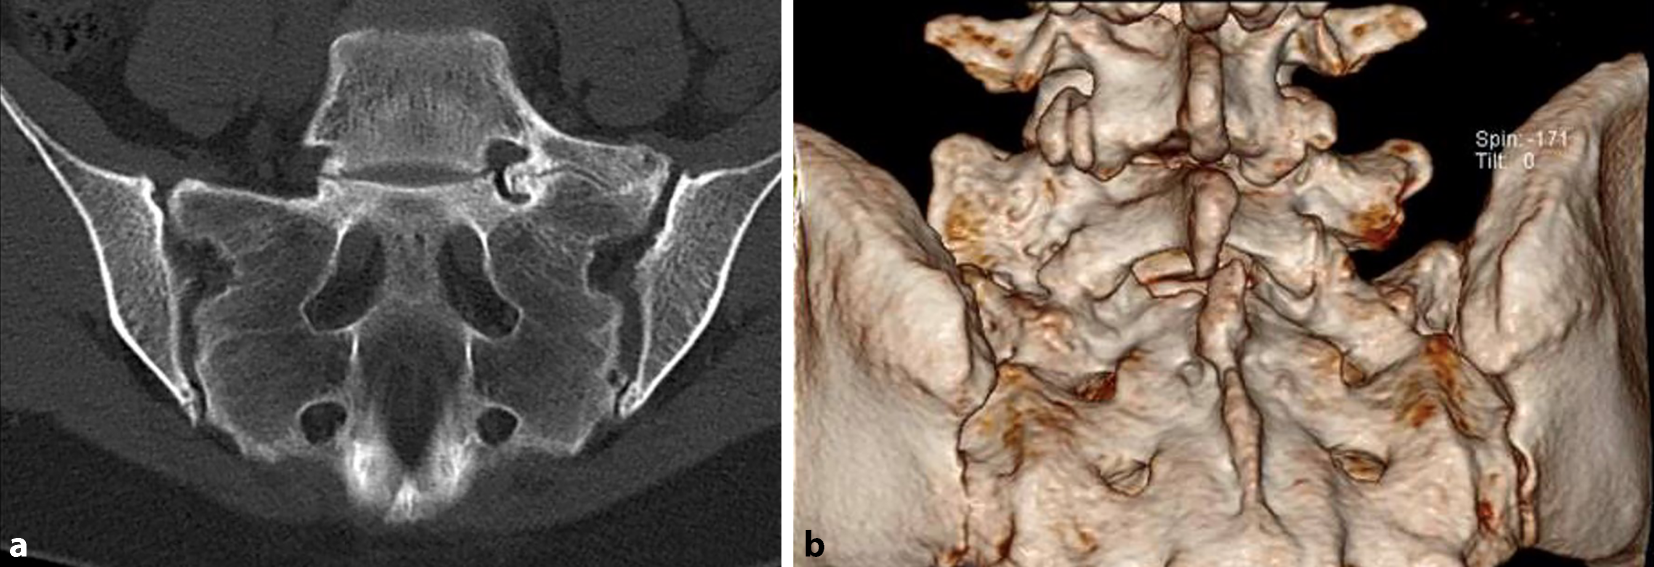

Eine MRT der LWS und des Sakrums dient dem Ausschluss lumbaler Differenzialdiagnosen, allen voran des ersten freien Bewegungssegmentes sowie dem Nachweis aktivierter Neogelenkbereiche (z. B. in STIR-Sequenzen). Eine CT des LSTV dient der optimalen dreidimensionalen Darstellung der knöchernen Anomalie inkl. möglicher Osteophyten im Neuroforamen (Abb. 2).

Abb. 2

CT-Darstellung (a) einer lumbosakralen Übergangsanomalie Typ Castellvi IIA mit 3‑D-Rekonstruktion (b)